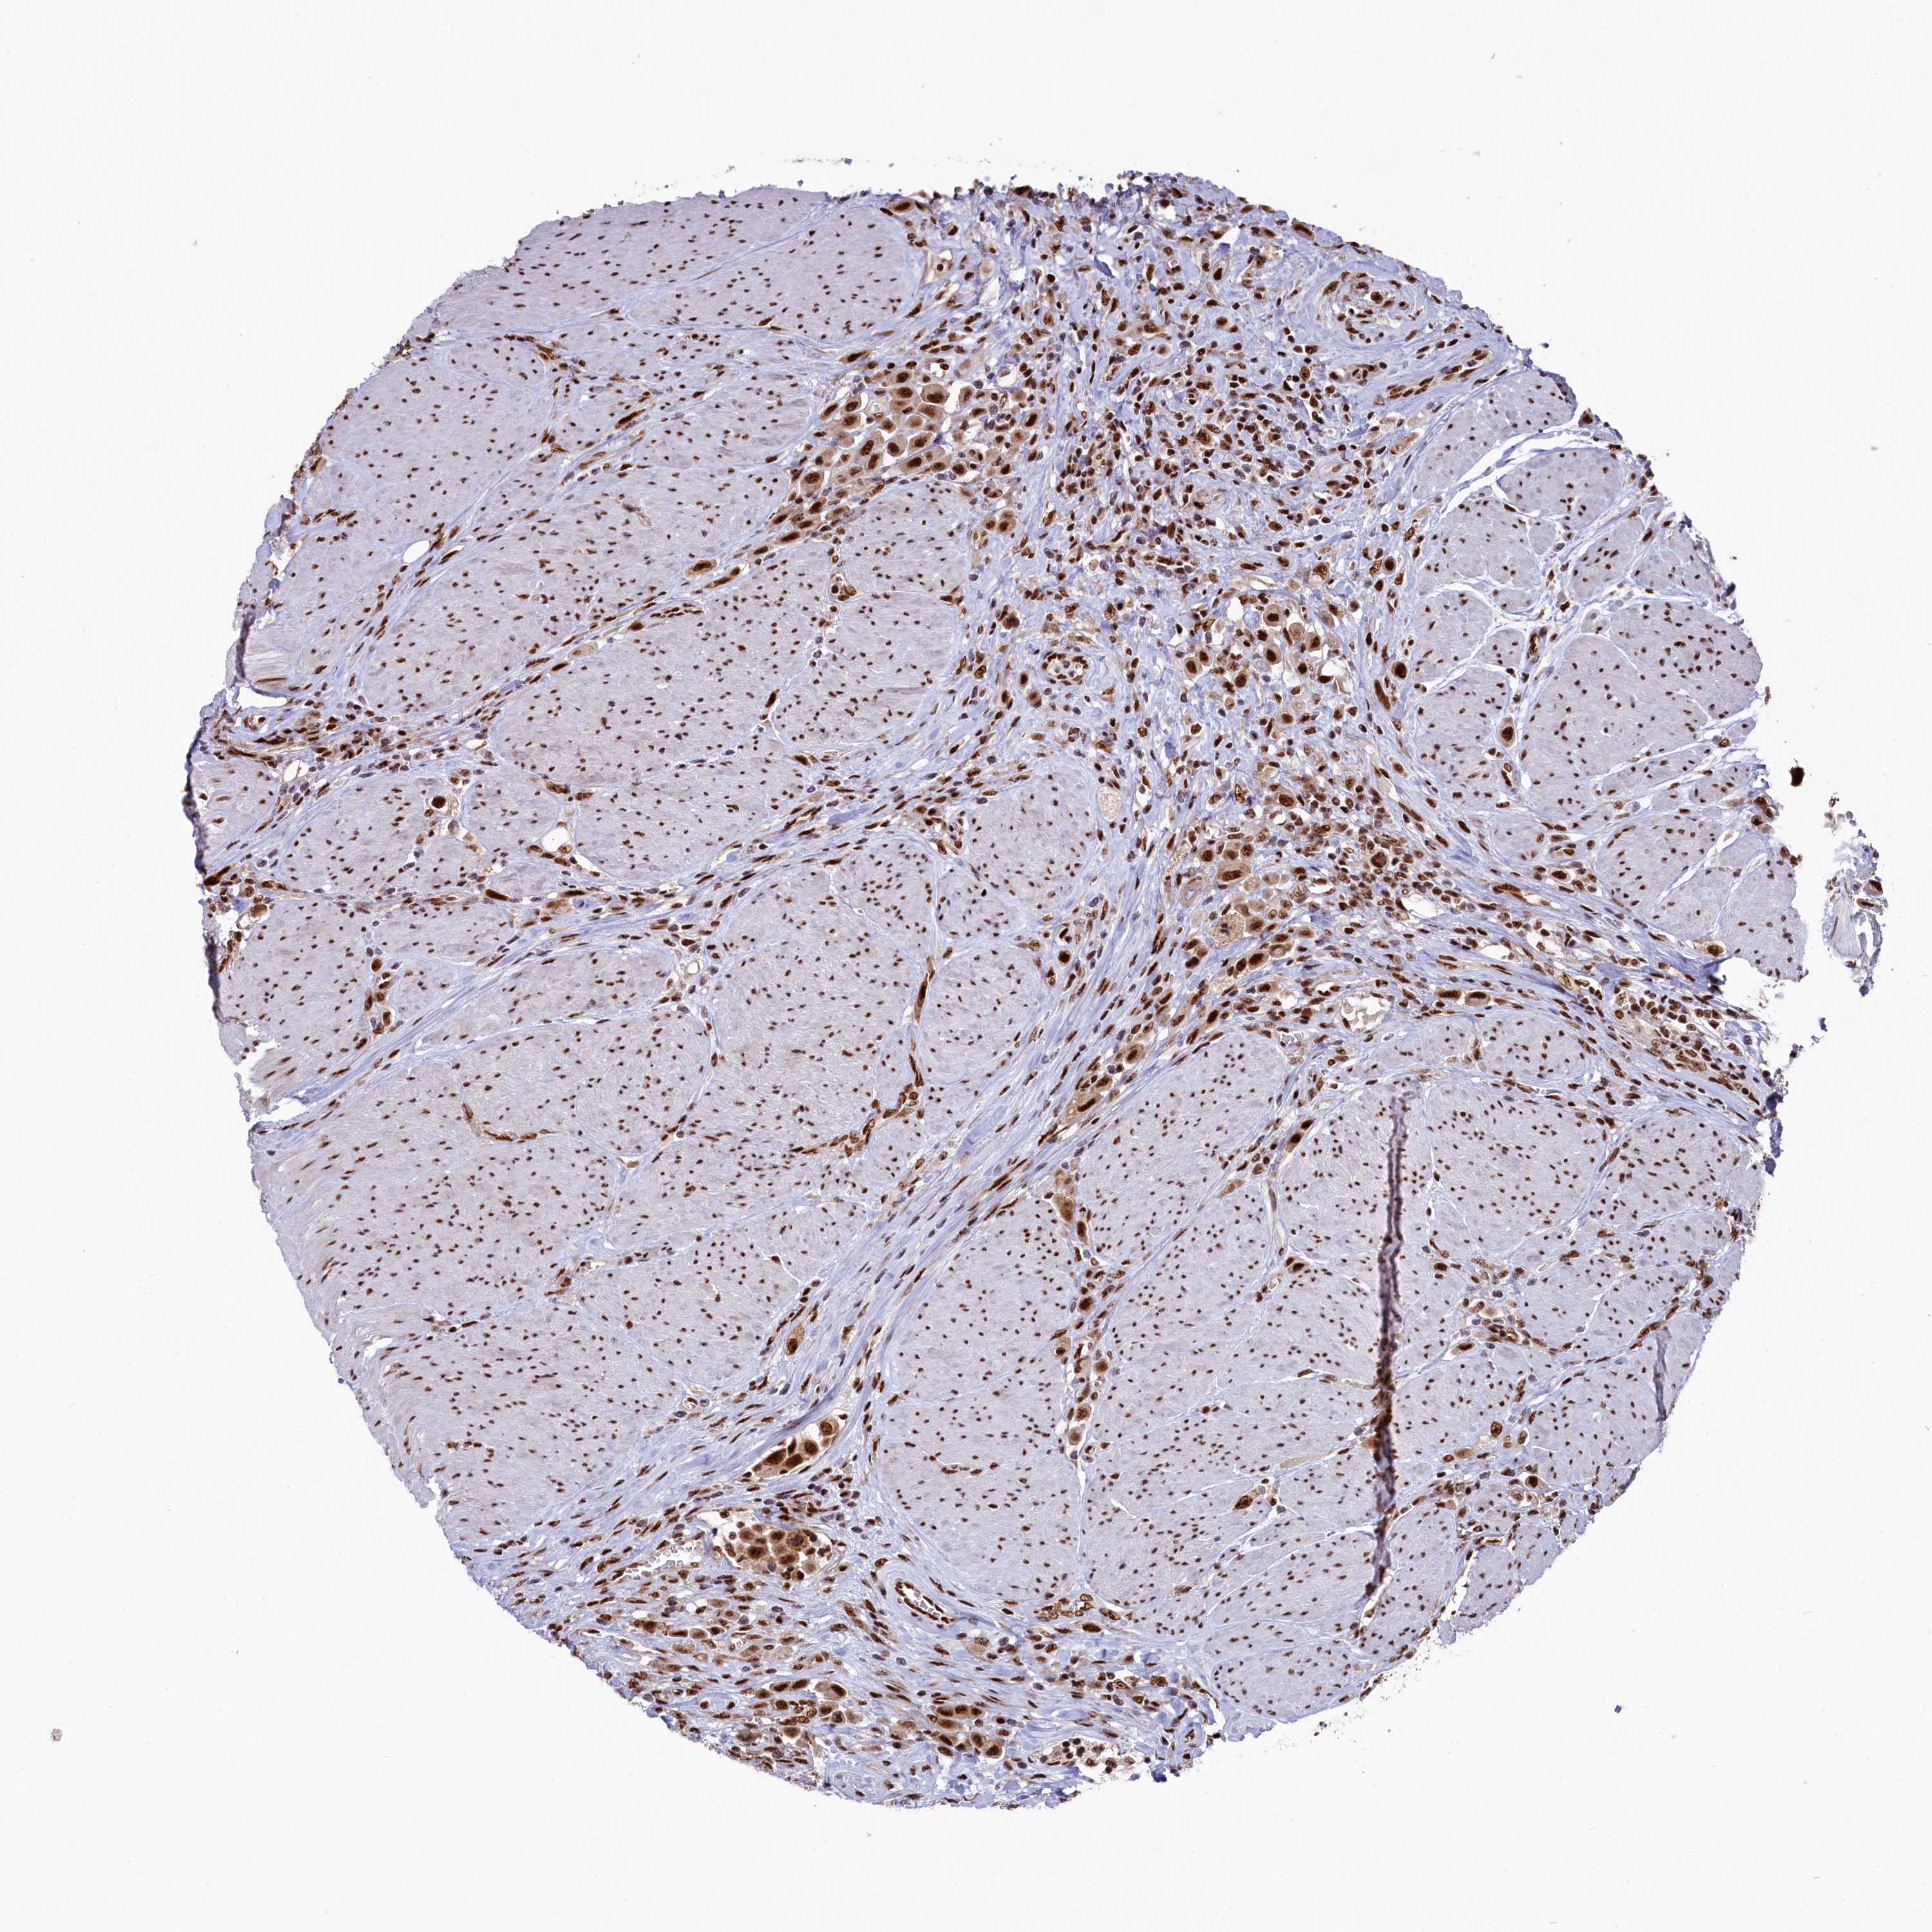

UROTHELIAL CANCER - Protein expressioni

A mouse-over function shows sample information and annotation data. Click on an image to view it in a full screen mode. Samples can be filtered based on level of antibody staining by selecting one or several of the following categories: high, medium, low and not detected. The assay and annotation is described here.

Note that samples used for immunohistochemistry by the Human Protein Atlas do not correspond to samples in the TCGA dataset.

Antibody stainingi

Antibody staining in the annotated cell types in the current human tissue is reported as not detected, low, medium, or high, based on conventional immunohistochemistry profiling in selected tissues. This score is based on the combination of the staining intensity and fraction of stained cells.

Each image is clickable and will lead to virtual microscopy that enables deeper exploration of all samples and also displays staining intensity scores, fraction scores and subcellular localization as well as patient and tissue information for each sample.

Antibody HPA041939

Staining

High

Medium

Low

Not detected

Intensity

Strong

Moderate

Weak

Negative

Quantity

>75%

75%-25%

<25%

None

Location

Nuclear

Cytoplasmic/membranous

Cytoplasmic/membranous,nuclear

Urothelial carcinoma, High grade

Urothelial carcinoma, Low grade

Urothelial carcinoma, NOS